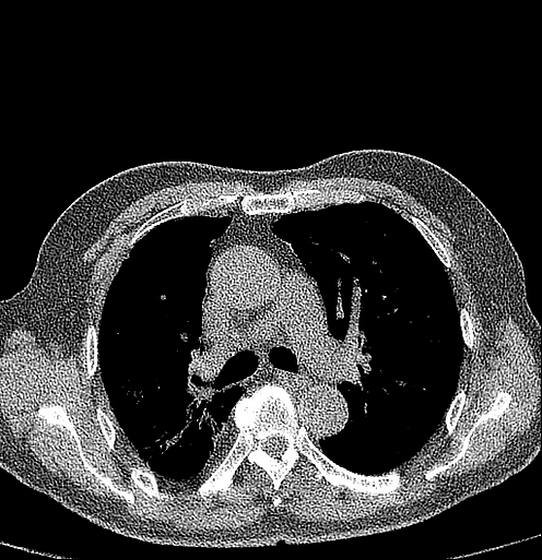

Internal bleeding

The internal bleeding is a life-threatening issue that may not show symptoms immediately. The CT scan machine can detect the presence of blood pooling in body cavities — such as the abdomen or chest — as well as identify ruptured blood vessels. It also helps visualize the extent of hemorrhaging, guiding critical decisions about urgent interventions, whether surgical, embolization, or other life-saving treatments to control bleeding.

Beyond simple imaging, a CT scan machine acts as a critical diagnostic partner in cardiology, delivering detailed visualizations that empower clinicians to detect, diagnose, and monitor complex cardiovascular conditions with confidence. Cardiovascular diseases can be detected:

Coronary Artery Disease (CAD)

CT scan machines provide detailed images of the coronary arteries — the vessels that supply blood to the heart — enabling doctors to detect even early-stage plaque buildup, narrowing, or blockages that can restrict blood flow. By clearly revealing the location and severity of these obstructions, CT imaging helps guide treatment decisions, such as whether medication, angioplasty, or surgery is most appropriate. It also supports long-term monitoring of coronary artery disease progression, ultimately improving patient outcomes and reducing the risk of heart attacks.

Aneurysms

An aneurysm is an abnormal bulge or weakened area in the wall of a blood vessel. Using detailed CT imaging, doctors can accurately visualize the size, shape, and precise location of an aneurysm — whether in the brain, aorta, or other vessels. This enables early diagnosis before a potential rupture, which is critical for preventing life-threatening complications. CT scan machines also help evaluate rupture risk by tracking growth over time and guide decisions regarding treatment, such as surgery, endovascular stent placement, or continued monitoring.

Blood Clots

CT scans are essential for rapidly detecting blood clots in critical areas such as the lungs (pulmonary embolism), brain (acute stroke), and deep veins (deep vein thrombosis). They